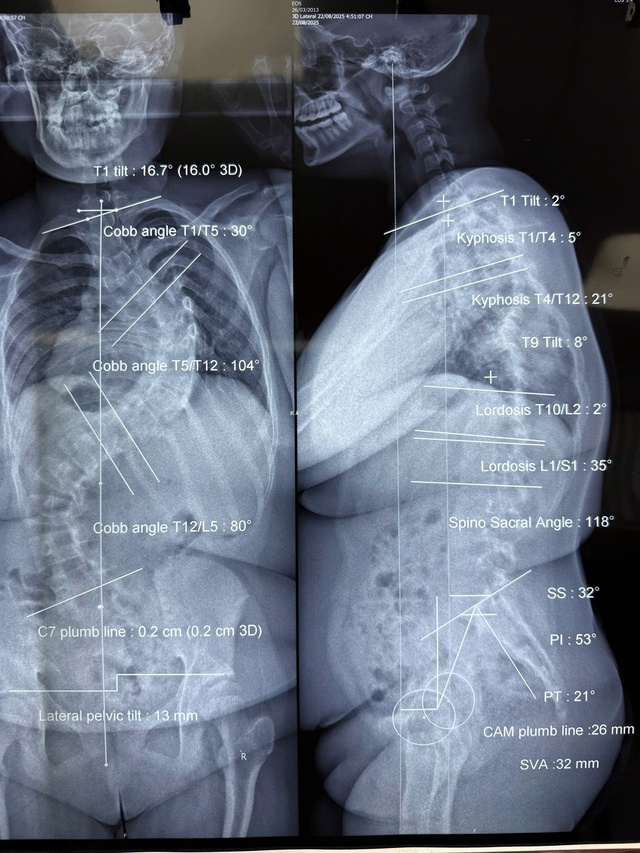

প্রথম কেসটি হল MNCL (১২ বছর বয়সী, হক মন জেলায় বসবাসকারী)। রোগীর স্কোলিওসিস অস্বাভাবিকভাবে দ্রুত অগ্রসর হয়েছিল। অস্ত্রোপচারের সময়, শিশুটির দুটি বড় বক্ররেখা ছিল, প্রধান বক্ররেখা ছিল ১০৪ ডিগ্রি এবং দ্বিতীয় বক্ররেখা ছিল ৮০ ডিগ্রি। অস্ত্রোপচারের জন্য অপেক্ষা করার ৭ মাস ধরে, মেরুদণ্ডের গঠন দ্রুত এবং তীব্রভাবে বিকৃত হতে থাকে।

অস্ত্রোপচারের আগে এমএনসিএল রোগীর মেরুদণ্ডের অবস্থা। ছবি: বিএসসিসি।